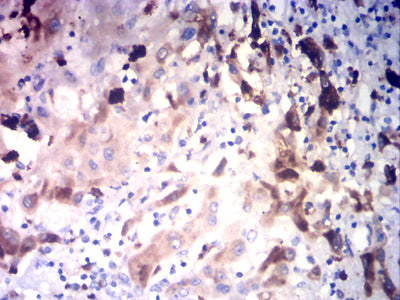

Immunohistochemical analysis of paraffin-embedded human liver cancer tissues using GLUL mouse mAb with DAB staining.